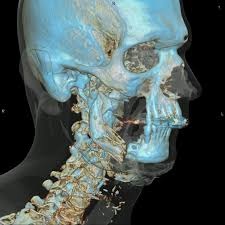

16 slice CT Scan

16 slice CT technology has dramatically advanced and broadened the range of CT applications to include orthopedics, angiography, cardiology, and more